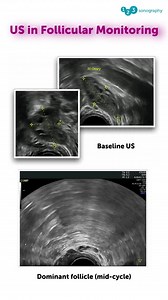

Effective ovulation induction requires precise serial ultrasound

…

806 views

3 months ago

Facebook

123sonography